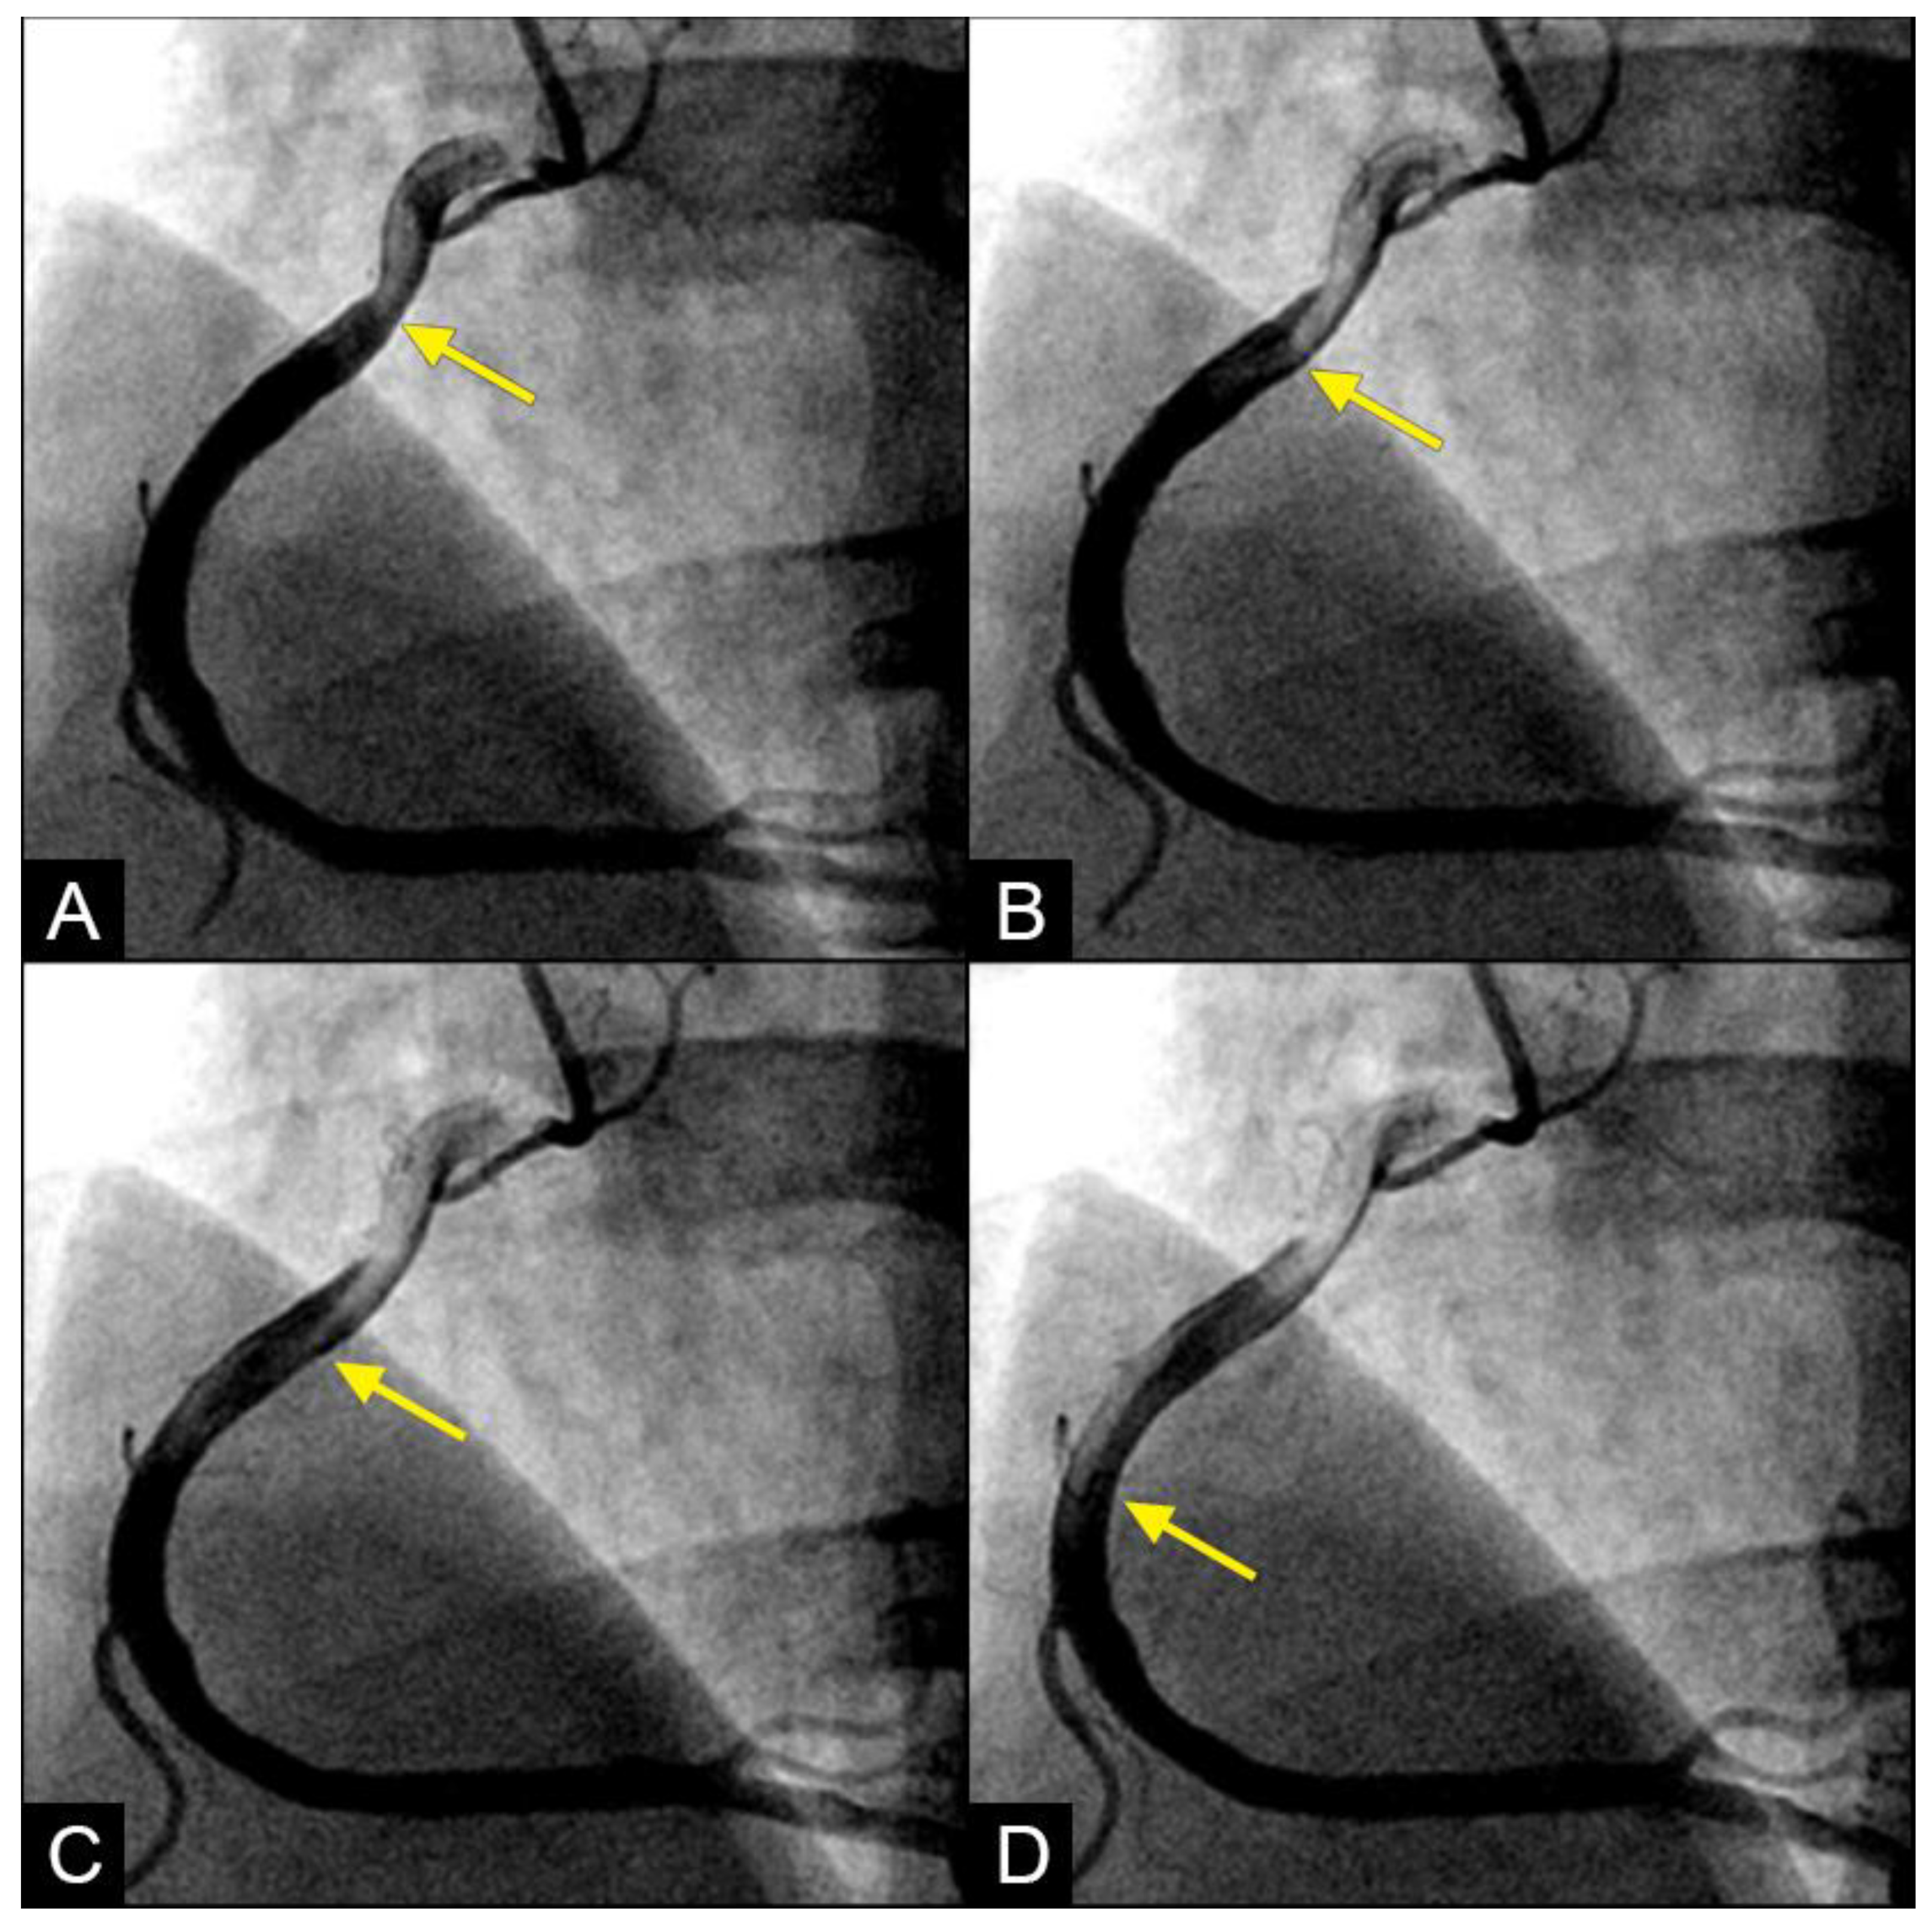

In the right coronary artery (RCA), during diastole, the blood flow could be observed over a black contrast background and identified clearly with well-organized flow and a sharp border, without mixing between blood and contrast, following the apex of the curves. By visual observation, this flow was laminar (Figure 5A–D) (Video S1).

Figure 5.

(A,B) Laminar flow. These four coronary images are in consecutive sequence. (A) This is the angiogram of the right coronary artery (RCA), which is filled with contrast (in black). (B) The blood (in white) is seen well organized with a sharp border and a pointed tip, curving along the apex (yellow arrow). (C,D) The blood (in white) is seen following the apex of the curves (yellow arrow). This is the laminar flow following the curves in a helical fashion.